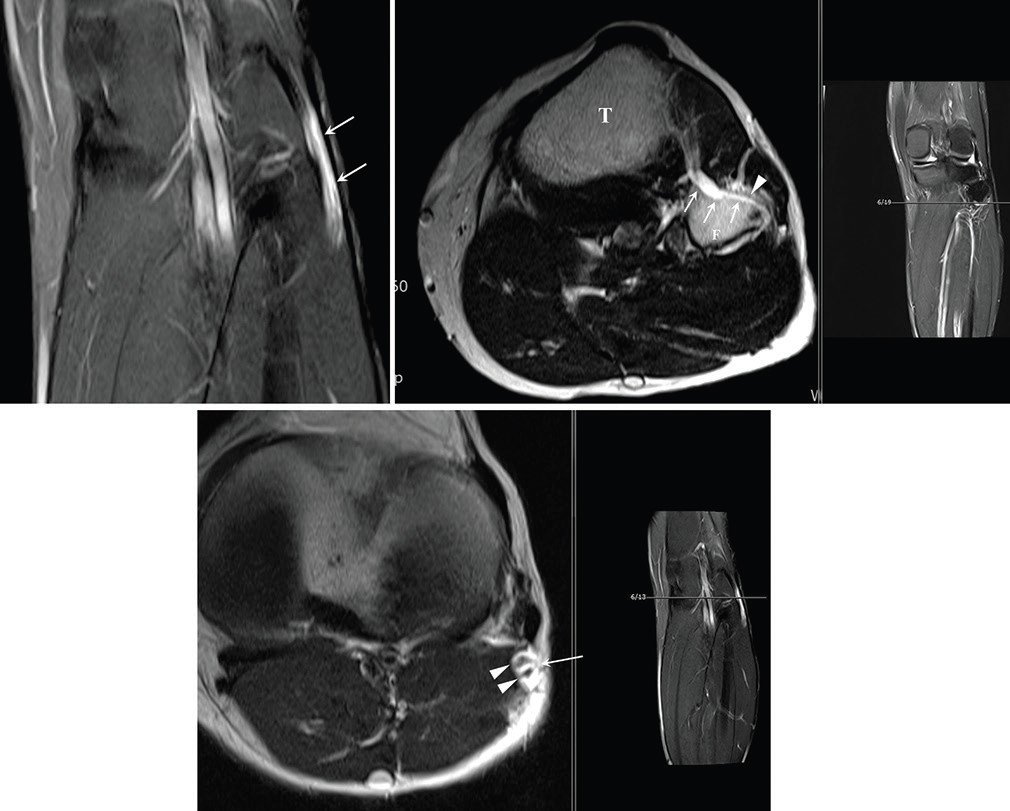

신경내 결절종은 관절 내부의 활액이 신경 지배 분지를 타고 역류해 신경 줄기 내부에 낭종을 형성하는 질환으로, 과거에는 원인이 불분명해 수술 후에도 재발이 잦고 영구적인 신경 손상을 남기는 난치성 질환으로 분류됐다.

당시 손 교수는 2016년 메이요 클리닉 연구팀이 최초 확인해 학계에 보고한 신경곁조직 아래막(subparaneurial) 결절종이라는 매우 희귀한 변이를 실제 임상 현장에서 발견하고, 이를 성공적으로 치료한 과정을 상세히 기술했다. 이는 기존에 알려진 신경외막(epineurium) 내부의 결절종과는 달리, 신경을 감싸는 더 깊은 층인 신경곁조직 아래 공간을 따라 낭종이 확산되는 독특한 병태생리를 규명한 중요한 전환점이 됐다.

특히 손 교수는 해당 연구를 통해 신경곁조직 아래막 결절종이 일반적인 결절종보다 신경 섬유에 더 밀착돼 있으며, 신경 줄기를 따라 매우 광범위하고 빠르게 전이될 수 있다는 사실을 확인했다. 이러한 특성 때문에 일반적인 낭종 제거술로는 완치가 어려운 만큼, 관절과 연결된 신경 분지를 근본적으로 차단하는 정교한 수술 기법 적용이 필요할 수 있음을 제시했다.

연구팀은 신경곁조직 아래막 결절종이 신경의 주 경로뿐만 아니라 해부학적으로 분리된 여러 신경 분지로까지 확산될 수 있다는 병태생리 파트 1, 2 논문을 완성했다. 이는 활액이 이동하는 미세한 해부학적 통로를 완벽히 이해해야만 재발 없는 치료가 가능하다는 사실을 과학적으로 입증한 것이다.